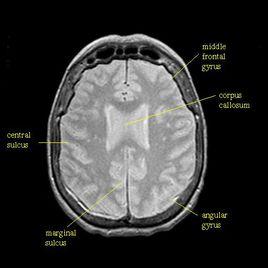

選取長TR(2000ms)和短TE(30~40ms),減少T1和T2對圖像影響,則信號強度與組織質子密度有關。

組織質子密度相差不大,則其對比度不強(10%-15%)。但有較高的信噪比,用於觀察細小結構的組織。

組織的H越大,信號就越強;H越小,信號就越弱。